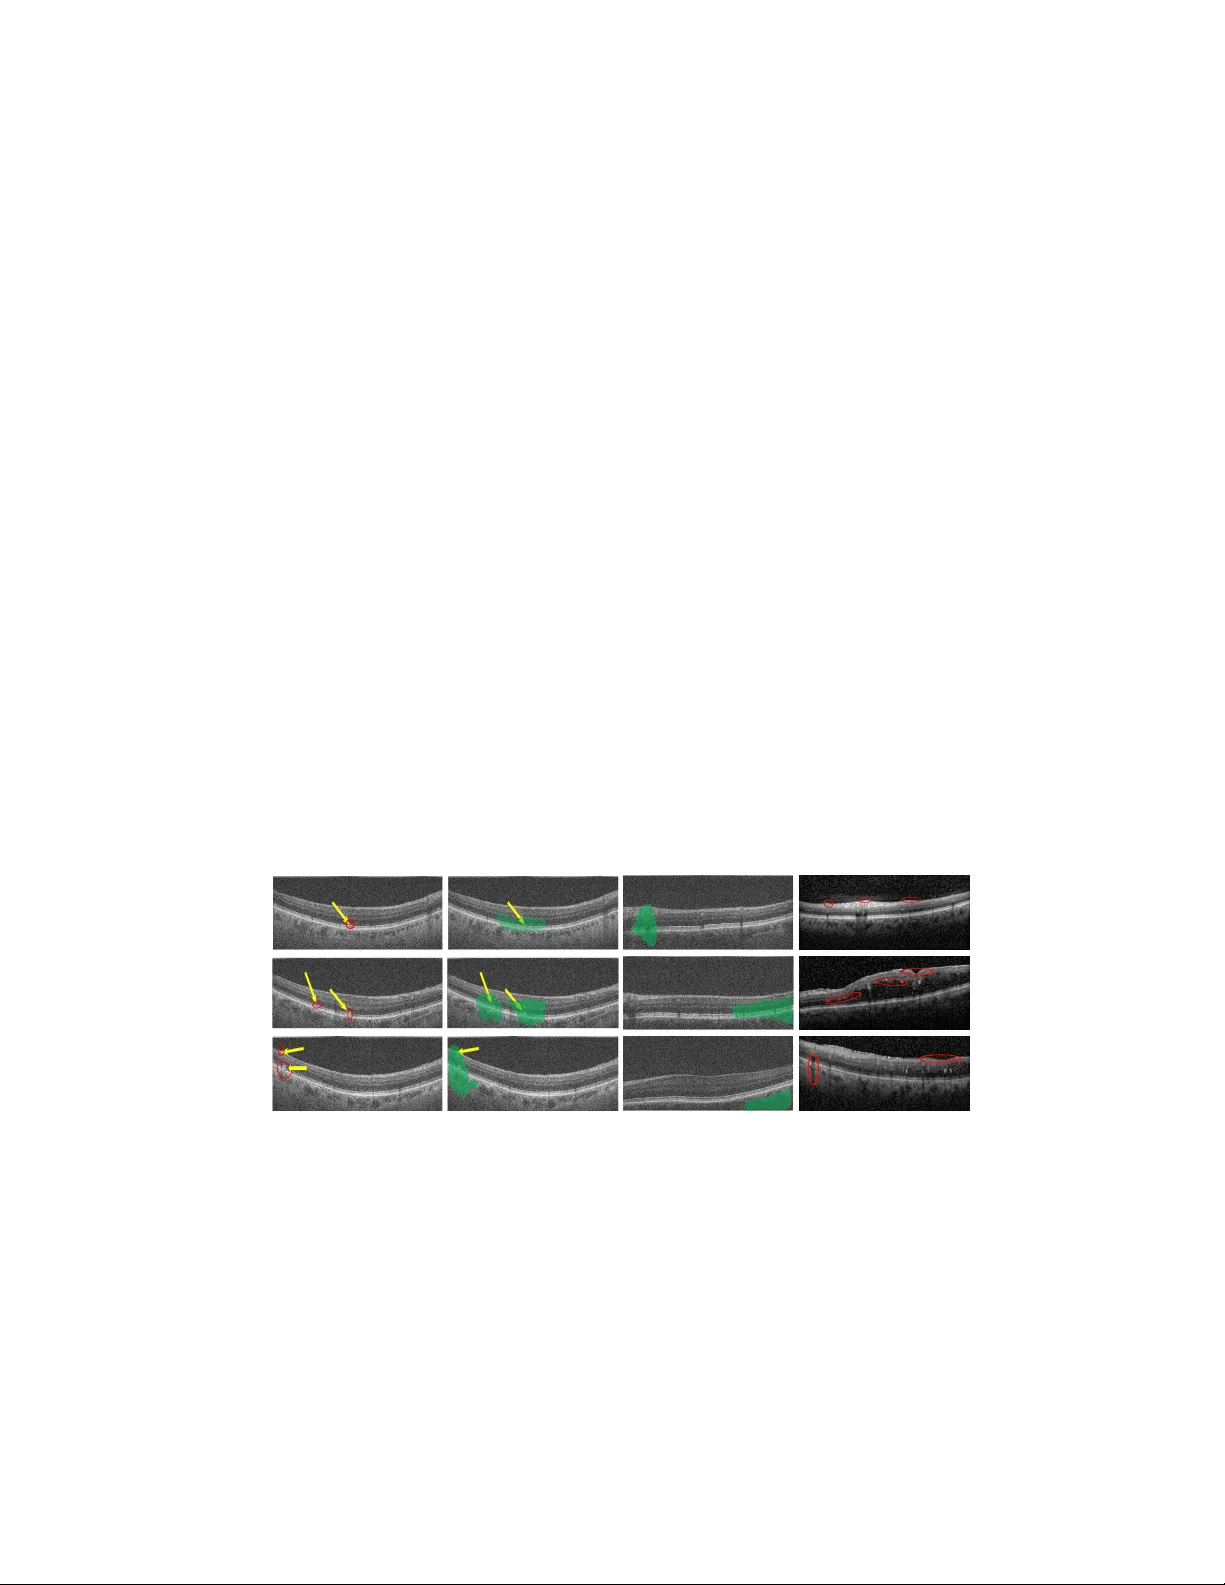

AMD Sev erit y Prediction And Explainabilit y Using Image Registration And Deep Em b edded Clustering Dw arik anath Mahapatra and Hidemasa Muta IBM Researc h Australia [dwarim,hidem]@au1.ibm.com. Abstract. W e prop ose a method to predict severit y of age related macu- lar degeneration (AMD) from input optical coherence tomography (OCT) images. Although there is no standard clinical severit y scale for AMD, w e lev erage deep learning (DL) based image registration and cluster- ing metho ds to identify diseased cases and predict their sev erity . Ex- p erimen ts demonstrate our approach’s disease classification performance matc hes state of the art metho ds. The predicted disease severit y p er- forms w ell on previously unseen data. Registration output pro vides bet- ter explainabilit y than class activ ation maps regarding label and severit y decisions. 1 In tro duction Most approaches to deep learning (DL) based medical image classification out- put a binary decision about presence or absence of a disease without explicitly justifying decisions. Moreov er, disease severit y prediction in an unsup ervised approac h is not clearly defined unless the lab els pro vide suc h information, as in diab etic retinopathy [1]. Diseases such as age related macular degeneration (AMD) do not hav e a standard clinical severit y scale and it is left to the ob- serv er’s exp ertise to assess severit y . While class activ ation maps (CAMs) [73] highligh t image regions that hav e high resp onse to the trained classifier they do not provide measurable parameters to explain the decision. Explainability of classifier decisions is an essential requirement of modern diagnosis systems. In this pap er w e propose a con volutional neural net work (CNN) based optical coherence tomography (OCT) image registration metho d that: 1) predicts the disease class of a given image (e.g., normal, diab etic macular edema (DME) or dry AMD); 2) uses registration output to grade disease sev erity on a normalized scale of [1 , 10] where 1 indicates normal and 10 indicates confirmed disease, and 3) provides explainability by outputting measurable parameters. Previous approaches to DL based image registration include regressors [70,68,4,5,23,75,63,28,22,11,21,35] and generative adversarial net works (GANs) [34,30,31,36,39,18]. [3,17,20,16,57,55] learn a parameterized registration function from training data without the need for simulated deformations in [68,53,33,25,34,24]. Although there is consider- able researc h in the field of in terpretable mac hine learning their application to 2 medical image analysis problems is limited [65,7,43,42,74,27,26,32]. The CAMs of [73] serv e as visualization aids rather than sho wing quantitativ e parameters. W e propose a nov el approach to o vercome the limitations of CAM, by pro vid- ing quanitativ e measures and their visualization for disease diagnosis based on image registration. Image registration makes the approac h fast and enables pro- jection of registration parameters to a linear scale for comparison against normal and diseased cases. It also provides localized and accurate quan titative output compared to CAMs. Our paper mak es the follo wing con tributions: 1) a nov el approac h for AMD severit y estimation using registration parameters and clus- tering; and 2) mapping registration output to a classification decision and output quan titative v alues explaining classification decision. 2 Metho d Our proposed metho d consists of: 1) atlas construction for differen t classes; 2) End to end training of a neural net work to estimate registration parameters and assign sev erity lab els; 3) Assign a test volume to a disease severit y scale, output its registration parameters and pro vide quan titatively in terpretable information. 2.1 A tlas Construction Using Groupwise Registration All normal v olumes are coarsely aligned using their p oin t cloud cluster and the iterated closest p oin t (ICP) algorithm. Groupwise registration using ITK [2] on all volumes giv es the atlas image A N . Each normal image is registered to A N using B-splines. The registration parameters are displacements of grid no des. They are easier to store and predict than a dense 3D deformation field and can b e used to generate the 3D deformation field. The abov e steps are used to obtain atlases for AMD ( A AM D ) and DME ( A DM E ). 2.2 Deep Em b edded Clustering Net work Deep embedded clustering [72,40,62,10,38,37,46] is an unsup ervised clustering approac h and giv es sup erior results than traditional clustering algorithms. T o cluster n p oin ts x i ∈ X n i =1 in to k clusters, each represen ted by a centroid µ j , j = 1 , · · · , k , DEC first transforms the data with a nonlinear mapping f θ : X 7→ Z , where θ are learnable parameters and Z is the latent feature space with lo wer dimensionality than X . Similarity b et ween em b edded p oin t z i and cluster cen troid µ j is given by the Student’s t-distribution as q ij =  1 + k z i − µ j k 2 /α  − α +1 2 P j 0  1 + k z i − µ j 0 k 2 /α  − α +1 2 , (1) where α = 1 for all exp eriments. DEC simultaneously learns k cluster centers in feature space Z and the parameters θ . It inv olv es: (1) parameter initializa- tion with a deep auto enco der [69] and (2) iterativ e parameter optimization b y 3 computing an auxiliary target distribution and minimizing the KullbackLeibler (KL) divergence. F or further details w e refer the reader to [72] 2.3 Estimation of Registration parameters Con ven tional registration metho ds output a deformation field from an input image pair while we join tly estimate the grid displacemen ts and severit y lab el using end to end training. Figure 1 depicts our workflo w. An input volume of dimension 512 × 1024 × N , N is n umber of slices, is con verted to a stack of N conv olution feature maps by do wnsampling to 256 × 512 × N and employing 1 × 1 con volution. The output is sho wn in Figure 1 as d256 fN k1, whic h indicates output maps of dimension ( d ) 256 × 512, N feature maps ( f ) and kernel dimension ( k ) of 1 × 1. The next conv olution lay er uses 3 × 3 kernels and outputs f = 32 feature maps. This is follow ed by a max p o oling step that reduces the map dimensions to 128 × 128 and the next conv olution la yer outputs 64 feature maps using 3 × 3 k ernels. After three further max p ooling and conv olution lay ers, the output of the “Enco der” stage are 128 feature maps of dimension 16 × 16. The Enco der output is used in tw o wa ys. The first branch is the input to the Deep Em b edded Clustering (DEC) netw ork (green b o xes depicting fully con- nected lay ers) that outputs a cluster lab el indicating severit y score. The second branc h from the Enco der is connected, along with the input volume’s disease lab el, to a fully connected (FC) lay er (orange b o xes) ha ving 4096 neurons. It is follow ed by t wo more FC la yers of 4096 neurons each and the final output is the set of registration parameters. The “Class Lab el id” (disease lab el of input v olume) and the Enco der output are combined using a global p o oling step. The motiv ation b ehind com bining the t wo is as follows: W e are interested to register, for example, a normal v olume to the normal atlas. The ground truth registration parameters of a normal v olume corresp ond to those obtained when registering the input volume to the normal atlas, and we wan t the regression netw ork to predict these parameters. F eeding the input volume’s actual disease lab el guides the regression netw ork to register the image to the corresponding atlas. 2.4 T raining Stage Implemen tation The en tire dataset is divided into training (70%), v alidation (10%) and test (20%) folds for eac h class. The DEC parameter initialization closely follows the steps outlined in [72]. The regression net work is trained using the input im- ages, their labels and the corresp onding registration parameters. W e augment the datasets 150 times by rotation and flipping and obtain their registration parameters with the corresp onding atlas. In the first phase of training only the regression netw ork is trained using mean squared error (MSE) loss for 50 epo chs to get an initial set of w eights. Subsequently , the DEC is trained using the out- put of the Enco der net w ork. After training is complete w e cluster the differen t v olumes and observe that 97 . 8% of the normal patients are assigned to clusters 1 , 2 and 3. 97 . 5% of Diab etic macular Edema (DME) cases are assigned to clus- ters 4 , 5 , 6 and 7, while 97 . 2% of AMD cases are assigned to clusters 8 , 9 and 10. 4 Fig. 1. Architecture of our proposed netw ork for AMD classification and sev erity es- timation. A regression netw ork for image registration and deep embedded clustering net work are combined to ac hieve our ob jectiv es. Th us the follo wing mapping betw een image lab els and cluster labels are obtained Normal ∈ { 1 , 2 , 3 } , DME ∈ { 4 , 5 , 6 , 7 } , and AMD ∈ { 8 , 9 , 10 } . 2.5 Predicting Sev erity of test image When a test image comes in we first use the trained DEC to predict the cluster lab el, which apart from providing disease severit y on a scale of [1 , 10] also gives the image’s disease class. The disease label is then used to predict the image’s registration parameters to the corresp onding atlas. Dep ending upon the desired lev el of granularit y of disease severit y the num b er of clusters can b e v aried to iden tify different cohorts that exhibit sp ecific traits. 3 Exp erimen tal Results W e demonstrate the effectiveness of our algorithm on a public dataset [66,19,29,61,59,60,58] consisting of OCT v olumes from 50 normal, 48 dry AMD, and 50 DME patients. The axial resolution of the images is 3 . 5 µ -m with scan dimension of 512 × 1024 pixels. The num b er of B-scans v aries betw een 19 , 25 , 31 , 61 p er volume in dif- feren t patients. The dataset is publicly av ailable at http://www.biosigdata.com. F or all registration steps w e used a grid size of 16 × 16 × 16. The n umber of predicted grid parameters are 16 3 = 4096 3.1 Registration Results The output registration parameters from our metho d are used to generate a de- formation field using B-splines and compared with outputs of other registration 5 metho ds. F or the purp ose of quantitativ e ev aluation w e applied simulated defor- mation fields and use differen t registration methods to reco ver the registration field. V alidation of accuracy is based on mean absolute distance (MAD) b et w een applied and reco vered deformation fields. W e also manually annotate retinal la y- ers and compute their 95% Hausdorff Distance ( H D 95 ) and Dice Metric (DM) b efore and after registration. Our method was implemented with Python and Keras, using SGD and Adam with β 1 = 0 . 93 and batc h normalization. T raining and test was p erformed on a NVIDIA T esla K40 GPU with 12 GB RAM. T able 1 compares results of the following metho ds: 1) R eg − D E C : Our prop osed metho d; 2) Reg N oDE C : Reg − D E C using only the registration without additional clustering; 3) V oxel M or ph : The metho d of [3,13,15,71,14,12,56]; 4) F low N et : - the registration method of [6,50,51,52,54,47,48]; 5) DI R N et : - the metho d of [70,45,44,49,64,41]; 6) Reg − k M eans - replacing DEC with kmeans clustering. Our metho d outperforms the state of the art DL based registration metho ds. 3.2 Classification Results T able 2 summarizes the performance of different metho ds on the test set for classifying b et ween normal, DME and AMD. Results are also sho wn for CNN based classification netw orks such as V GG-16 [67], Resnet [8] and DenseNet [9], three of the most widely used classification CNNs and the multiscale CNN ensem ble of [66] that serv es as the baseline for this dataset. Our prop osed metho d outp erforms standard CNN arc hitectures, th us proving the efficacy of com bining registration with clustering for classification tasks. It also shows Reg − D E C ’s adv antages of low er computing time and fewer training parameters. 3.3 Iden tification of Disease Subgroups And Explainability Besides predicting a disease lab el and severit y score, our metho d pro vides ex- plainabilit y behind the decision. F or a given test image and its predicted registra- tion parameters w e calculate its l 2 distance from eac h of the 10 cluster cen ters to giv e us a single v alue quan tifying the sample’s similarity with each disease clus- ter. Let the sample s b e assigned to cluster i ∈ [1 , 10] and let the corresp onding Bef. After Registration Reg Reg-DEC Reg N oD E C Reg-kMeans DIRNet Flo wNet V oxelMorph DM(%) 78.9 89.3 85.9 84.8 83.5 87.6 88.0 HD 95 (mm) 12.9 6.9 8.4 8.7 9.8 7.5 7.4 MAD 13.7 7.3 8.9 10.3 9.1 8.6 7.9 Time(s) 0.5 0.4 0.6 0.5 0.6 0.6 T able 1. Image registration results from differen t metho ds. T ime indicates computa- tion time in seconds. 6 l 2 distances of s to each cluster b e d i . W e calculate a normalized v alue p d =     d i − d 1 d 10 − d i     , (2) where p d giv es a probabilit y of the test sample reaching the highest severit y score. It is also a severit y score on a normalized scale of [0 , 1]. Scores from m ultiple visits help to build a patien t sev erity profile for analysing differen t factors b ehind increase or decrease of severit y , as well as the corresp onding rate of c hange. The rate of sev erity change is an important factor to determine a p ersonalized diagnosis plan. p d is different from the class probability obtained from a CNN classifier. The classifier probability is its confidence in the decision while p d giv es the probability of transitioning to the most sev ere stage. T ables 1,2 demonstrate Reg − D E C ’s superior p erformance for classification and registration. T o determine Reg − D E C ’s effectiveness in predicting disease sev erity of classes not part of the training data, we train our severit y prediction net work on normal and AMD images only , leaving out the DME affected images. W e keep the same n umber of clusters (i.e., 10) as be fore. Since there are no DME images and num ber of clusters is unc hanged, assignment of images to clusters is differen t than b efore. In this case 96 . 4% of AMD images are assigned to clusters 8 , 9 , 10 which is a drop of 0 . 8% than the previous assignment while 96 . 5% of normal samples are assigned to clusters 1 , 2 , 3 which is decrease of 1 . 3%. W e see few er images in clusters 4 , 5 , 6 , 7 although the ma jority of original assignmen ts of normal and AMD cases are unchanged. When w e use this trained mo del on the DME images we find that 96 . 9% of the images are assigned to clusters 4 , 5 , 6 , 7, a decrease of 0 . 9% from before. The ab o ve results lead to the follo wing conclusions: 1) Reg − D E C ’s performance reduces by 0 . 9% for DME and maximum of 1 . 3% (for Normal images) when DME images were not part of the training data. This is not a significant drop indicating Reg − D E C ’s capacit y to identify sub-groups that were not part of the training data. 2) Using k-means clustering do es not give same p erformance levels demonstrating that end to end feature learning com bined with clustering gives muc h b etter results than p erforming the steps separately . Reg − D E C accurately predicts disease sev erity even though there is no standard sev erity grading scale. Severit y scale also identifies sub-groups from the p opulation with a sp ecific disease activit y . Figure 2 first and second columns, respectively , sho w AMD images accurately classified by R eg − D E C and DenseNet. The yello w arro ws highlight regions of Reg − D E C V GG 16 ResN et 50 D enseN et DEC kmeans MultCNN [66] Sen 93.6 91.7 92.5 92.6 89.5 85.7 92.5 Sp e 94.3 92.8 93.6 93.5 90.6 86.8 93.4 A UC 96.4 94.1 95.2 95.3 91.9 87.7 95.2 Time(h) 4.3 16.7 12.4 13.6 2.5 0.5 15.1 T able 2. Classification results for AMD, DME and normal on the test set using dif- feren t netw orks. Time indicates training time in hours. 7 abnormalit y iden tified b y clinicians. Red ellipses (in first column) show the region of disease activit y . The length of ma jor axis quan tifies magnitude of displacemen t of the corresp onding grid point, and the orientation indicates direction. The lo cal displacemen t magnitude is prop ortional to disease severit y while the orientation iden tifies the exact location. The second column shows the corresponding CAMs obtained from DenseNet (region highlighted in green). Although the CAMs in- clude the region of disease activit y it does not localize it accurately and is spread out, nor do es it output a measurable v alue. By dividing the displacement mag- nitude with the distance b et ween the grid p oin ts w e get a v alue very close to p d . The adv antages of our registration based method is ob vious since it pinp oin ts abnormalit y and quantifies it in terms of displacement magnitude and angle. Figure 2 third column sho ws examples of normal images that were rightly classified b y Reg − D E C but incorrectly classified as AMD by DenseNet. The green regions highlight disease activt y as identified by DenseNet, which is er- roneous since there are no abnormalities here. Reg − DE C do es not show any lo calization of pathologies in these examples. The fourth column sho ws examples of DME that w ere righ tly identified b y Reg − D E C , despite not b eing being part of the training data, alongwith red ellipses sho wing localized regions of disease activit y . They were assigned to clusters 4 , 6 , 7 resp ectiv ely . The CNNs trained to classify AMD and normal w ould mostly classify the second and third image as diseased while the first image w as usually classified as normal because of its similar app earance to some normal images. Th us, our metho d iden tifies different patien t cohorts despite those not b eing part of the training data. (a) (b) (c) (d) Fig. 2. Example of misclassified images. Y ello w arrows sho w p ositions of diseased ac- tivit y in AMD images. (a) predictions by Reg − D E C and quanitfication of disease activit y; (b) CAMs by DenseNet; (c) normal images inaccurately classified as AMD by DenseNet with CAMs; (d) DME images correctly classified by Reg − DE C . Red circles are prop ortional to disease severit y . 8 4 Conclusion W e prop ose a metho d to predict disease severit y from retinal OCT images despite there being no lab els pro vided for the disease severit y . CNN regressor predicts registration parameters for a giv en test image which are undergo clustering to output a disease severit y scale and a disease probability score in addition to the classification label (diseased or normal). Experimental results sho w our propo sed metho d ac hieves b etter registration and classification p erformance compared to existing approaches. W e are able to identify distinct patien t cohorts not part of training data. Our approac h also pro vides explainabilit y b ehind the classification decision by quantifying disease activity from the registration parameters. References 1. h ttps://www.eyepacs.com 2. ”the insigh t segmentation and registration to olkit” www.itk.org 3. Balakrishnan, G., Zhao, A., Sabuncu, M., Guttag, J.: An supervised learning model for deformable medical image registration. In: Pro c. CVPR. pp. 9252–9260 (2018) 4. Bozorgtabar, B., Mahapatra, D., v on T eng, H., Pollinger, A., Ebner, L., Thiran, J.P ., M.Reyes.: Informative sample generation using class a ware generative ad- v ersarial netw orks for classification of chest xrays. Computer Vision and Image Understanding 184, 57–65 (2019) 5. D. Mahapatra, B.B., Garna vi, R.: Image sup er-resolution using progressiv e gen- erativ e adversarial netw orks for medical image analysis. Computerized Medical Imaging and Graphics 71(1), 30–39 (2019) 6. Doso vitskiy , A., Fischer, P ., et. al.: Flownet: Learning optical flow with conv olu- tional net works. In: In Pro c. IEEE ICCV. pp. 2758–2766 (2015) 7. Graziani, M., Andrearczyk, V., Mller, H.: Regression concept v ectors for bidirec- tional explanations in histopathology . In: In Pro c. MICCAI-iMIMIC. pp. 124–132 (2018) 8. He, K., Zhang, X., Ren, S., Sun, J.: Deep residual learning for image recognition. In: In Pro c. CVPR (2016) 9. Huang, G., Liu, Z., v an der Maaten, L., W einberger, K.: Densely connected con- v olutional netw orks. In: https://arxiv.org/abs/1608.06993, (2016) 10. Kuang, H., Guthier, B., Saini, M., Mahapatra, D., Saddik, A.E.: A real-time smart assistan t for video surveillance through handheld devices. In: In Pro c: ACM Intl. Conf. Multimedia. pp. 917–920 (2014) 11. Li, Z., Mahapatra, D., J.Tielbeek, Stoker, J., v an Vliet, L., V os, F.: Image registra- tion based on auto correlation of lo cal structure. IEEE T rans. Med. Imaging 35(1), 63–75 (2016) 12. Mahapatra, D.: Neonatal brain mri skull stripping using graph cuts and shape priors. In: In Pro c: MICCAI w orkshop on Image Analysis of Human Brain Dev el- opmen t (IAHBD) (2011) 13. Mahapatra, D.: Cardiac lv and rv segmentation using m utual context information. In: Pro c. MICCAI-MLMI. pp. 201–209 (2012) 14. Mahapatra, D.: Group wise registration of dynamic cardiac p erfusion images using temp oral information and segmentation information. In: In Pro c: SPIE Medical Imaging (2012) 9 15. Mahapatra, D.: Landmark detection in cardiac mri using learned lo cal image statis- tics. In: Proc. MICCAI-Statistical Atlases and Computational Mo dels of the Heart. Imaging and Mo delling Challenges (ST ACOM). pp. 115–124 (2012) 16. Mahapatra, D.: Skull stripping of neonatal brain mri: Using prior shap e information with graphcuts. J. Digit. Imaging 25(6), 802–814 (2012) 17. Mahapatra, D.: Cardiac image segmen tation from cine cardiac mri using graph cuts and shap e priors. J. Digit. Imaging 26(4), 721–730 (2013) 18. Mahapatra, D.: Cardiac mri segmentation using mutual context information from left and righ t ven tricle. J. Digit. Imaging 26(5), 898–908 (2013) 19. Mahapatra, D.: Graph cut based automatic prostate segmentation using learned seman tic information. In: Pro c. IEEE ISBI. pp. 1304–1307 (2013) 20. Mahapatra, D.: Join t segmentation and group wise registration of cardiac perfusion images using temp oral information. J. Digit. Imaging 26(2), 173–182 (2013) 21. Mahapatra, D.: Automatic cardiac segmentation using semantic information from random forests. J. Digit. Imaging. 27(6), 794–804 (2014) 22. Mahapatra, D.: Com bining m ultiple expert annotations using semi-sup ervised learning and graph cuts for medical image segmentation. Computer Vision and Image Understanding 151(1), 114–123 (2016) 23. Mahapatra, D.: Semi-sup ervised learning and graph cuts for consensus based med- ical image segmen tation. Pattern Recognition 63(1), 700–709 (2017) 24. Mahapatra, D., Bozorgtabar, S., Hewa vitahranage, S., Garnavi, R.: Image super resolution using generative adversarial netw orks and lo cal saliencymaps for retinal image analysis,. In: In Proc. MICCAI. pp. 382–390 (2017) 25. Mahapatra, D., Bozorgtabar, S., Thiran, J.P ., Rey es, M.: Efficient active learning for image classification and segmentation using a sample selection and conditional generativ e adversarial netw ork. In: In Pro c. MICCAI (2). pp. 580–588 (2018) 26. Mahapatra, D., Buhmann, J.: Obtaining consensus annotations for retinal image segmen tation using random forest and graph cuts. In: In Proc. OMIA. pp. 41–48 (2015) 27. Mahapatra, D., Buhmann, J.: Visual saliency based active learning for prostate mri segmen tation. In: In Pro c. MLMI. pp. 9–16 (2015) 28. Mahapatra, D., Buhmann, J.: Visual saliency based active learning for prostate mri segmen tation. SPIE Journal of Medical Imaging 3(1) (2016) 29. Mahapatra, D., Buhmann, J.: Automatic cardiac rv segmen tation using semantic information with graph cuts. In: Proc. IEEE ISBI. pp. 1094–1097 (2013) 30. Mahapatra, D., Buhmann, J.: Analyzing training information from random forests for improv ed image segmen tation. IEEE T rans. Imag. Proc. 23(4), 1504–1512 (2014) 31. Mahapatra, D., Buhmann, J.: Prostate mri segmentation using learned semantic kno wledge and graph cuts. IEEE T rans. Biomed. Engg. 61(3), 756–764 (2014) 32. Mahapatra, D., Buhmann, J.: A field of exp erts model for optic cup and disc segmen tation from retinal fundus images. In: In Proc. IEEE ISBI. pp. 218–221 (2015) 33. Mahapatra, D., Ge, Z.: T raining data independent image registration with gans using transfer learning and segmen tation information. In: In Pro c. IEEE ISBI (2019) 34. Mahapatra, D., Ge, Z., Sedai, S., Chakra vort y ., R.: Joint registration and segmen- tation of xray images using generative adversarial net works. In: In Pro c. MICCAI- MLMI. pp. 73–80 (2018) 10 35. Mahapatra, D., Gilani, S., Saini., M.: Coherency based spatio-temporal saliency detection for video ob ject segmentation. IEEE Journal of Selected T opics in Signal Pro cessing. 8(3), 454–462 (2014) 36. Mahapatra, D., J.Tielb eek, Mak any anga, J., Stoker, J., T aylor, S., V os, F., Buh- mann, J.: Automatic detection and segmentation of crohn’s disease tissues from ab dominal mri. IEEE T rans. Med. Imaging 32(12), 1232–1248 (2013) 37. Mahapatra, D., J.Tielb eek, Mak any anga, J., Stoker, J., T aylor, S., V os, F., Buh- mann, J.: Active learning based segmentation of crohn’s disease using principles of visual saliency . In: Pro c. IEEE ISBI. pp. 226–229 (2014) 38. Mahapatra, D., J.Tielb eek, Mak any anga, J., Stoker, J., T aylor, S., V os, F., Buh- mann, J.: Combiningm ultiple exp ert annotations using semi-sup ervised learning and graph cuts for crohns disease segmentation. In: In Pro c: MICCAI-ABD (2014) 39. Mahapatra, D., J.Tielb eek, V os, F., Buhmann, J.: A sup ervised learning approach for crohn’s disease detection using higher order image statistics and a nov el shape asymmetry measure. J. Digit. Imaging 26(5), 920–931 (2013) 40. Mahapatra, D., Li, Z., V os, F., Buhmann, J.: Joint segmentation and groupwise registration of cardiac dce mri using sparse data representations. In: In Proc. IEEE ISBI. pp. 1312–1315 (2015) 41. Mahapatra, D., Routra y , A., Mishra, C.: An active snak e mo del for classification of extreme emotions. In: IEEE International Conference on Industrial T echnology (ICIT). pp. 2195–2199 (2006) 42. Mahapatra, D., Roy , P ., Sedai, S., Garna vi, R.: A cnn based neurobiology inspired approac h for retinal image quality assessment. In: In Pro c. EMBC. pp. 1304–1307 (2016) 43. Mahapatra, D., Roy , P ., Sedai, S., Garnavi, R.: Retinal image quality classification using saliency maps and cnns. In: In Proc. MICCAI-MLMI. pp. 172–179 (2016) 44. Mahapatra, D., Roy , S., Sun, Y.: Retriev al of mr kidney images by incorp orating spatial information in histogram of low level features. In: In 13th International Conference on Biomedical Engineering (2008) 45. Mahapatra, D., Saini, M., Sun, Y.: Illumination in v arian t trac king in office envi- ronmen ts using neurobiology-saliency based particle filter. In: IEEE ICME. pp. 953–956 (2008) 46. Mahapatra, D., Sch ¨ u ffler, P ., Tielb eek, J., V os, F., Buhmann, J.: Semi-supervised and activ e learning for automatic segmentation of crohn’s disease. In: Pro c. MIC- CAI, P art 2. pp. 214–221 (2013) 47. Mahapatra, D., Sun, Y.: Nonrigid registration of dynamic renal MR images using a saliency based MRF model. In: Pro c. MICCAI. pp. 771–779 (2008) 48. Mahapatra, D., Sun, Y.: Registration of dynamic renal MR images using neurobi- ological mo del of saliency . In: Pro c. ISBI. pp. 1119–1122 (2008) 49. Mahapatra, D., Sun, Y.: Using saliency features for graphcut segmentation of p er- fusion kidney images. In: In 13th In ternational Conference on Biomedical Engi- neering (2008) 50. Mahapatra, D., Sun, Y.: Joint registration and segmentation of dynamic cardiac p erfusion images using mrfs. In: Pro c. MICCAI. pp. 493–501 (2010) 51. Mahapatra, D., Sun., Y.: An mrf framew ork for join t registration and segmen tation of natural and perfusion images. In: Pro c. IEEE ICIP . pp. 1709–1712 (2010) 52. Mahapatra, D., Sun, Y.: Retriev al of perfusion images using cosegmen tation and shap e context information. In: Pro c. APSIP A Annual Summit and Conference (ASC) (2010) 11 53. Mahapatra, D., Sun, Y.: Rigid registration of renal p erfusion images using a neu- robiology based visual saliency mo del. EURASIP Journal on Image and Video Pro cessing. pp. 1–16 (2010) 54. Mahapatra, D., Sun, Y.: A saliency based mrf metho d for the joint registration and segmen tation of dynamic renal mr images. In: Pro c. ICDIP (2010) 55. Mahapatra, D., Sun, Y.: Mrf based intensit y in v arian t elastic registration of cardiac p erfusion images using saliency information. IEEE T rans. Biomed. Engg. 58(4), 991–1000 (2011) 56. Mahapatra, D., Sun, Y.: Orientation histograms as shap e priors for left ven tricle segmen tation using graph cuts. In: In Pro c: MICCAI. pp. 420–427 (2011) 57. Mahapatra, D., Sun, Y.: Integrating segmen tation information for improv ed mrf- based elastic image registration. IEEE T rans. Imag. Proc. 21(1), 170–183 (2012) 58. Mahapatra, D., Ti elb eek, J., Buhmann, J., V os, F.: A supervised learning based ap- proac h to detect crohn’s disease in ab dominal mr v olumes. In: Pro c. MICCAI work- shop Computational and Clinical Applications in Ab dominal Imaging(MICCAI- ABD). pp. 97–106 (2012) 59. Mahapatra, D., Tielb eek, J., V os, F., ., J.B.: Crohn’s disease tissue segmen tation from ab dominal mri using seman tic information and graph cuts. In: Pro c. IEEE ISBI. pp. 358–361 (2013) 60. Mahapatra, D., Tielb eek, J., V os, F., Buhmann, J.: Lo calizing and segmenting crohn’s disease affected regions in ab dominal mri using nov el con text features. In: Pro c. SPIE Medical Imaging (2013) 61. Mahapatra, D., Tielb eek, J., V os, F., Buhmann, J.: W eakly supervised semantic segmen tation of crohn’s disease tissues from ab dominal mri. In: Pro c. IEEE ISBI. pp. 832–835 (2013) 62. Mahapatra, D., V os, F., Buhmann, J.: Crohn’s disease segmentation from mri using learned image priors. In: In Proc. IEEE ISBI. pp. 625–628 (2015) 63. Mahapatra, D., V os, F., Buhmann, J.: Active learning based segmentation of crohns disease from abdominal mri. Computer Methods and Programs in Biomedicine 128(1), 75–85 (2016) 64. Mahapatra, D., Winkler, S., Y en, S.: Motion saliency outw eighs other low-lev el features while w atching videos. In: SPIE HVEI. pp. 1–10 (2008) 65. P ereira, S., Meier, R., Alves, V., Reyes, M., Silv a., C.: Automatic brain tumor grading from mri data using conv olutional neural net w orks and qualit y assessmen t. In: In Pro c. MICCAI-iMIMIC. pp. 106–114 (2018) 66. Rasti, R., Rabbani, H., Mehri, A., Ha jizadeh, F.: Macular oct classification using a m ulti-scale conv olutional neural net work ensemble. IEEE T rans. Med. Imag. 37(4), 1024–1034 (2018) 67. Simon yan, K., Zisserman., A.: V ery deep conv olutional net works for large-scale image recognition. CoRR abs/1409.1556 (2014) 68. Sok o oti, H., de V os, B., Berendsen, F., Lelieveldt, B., Isgum, I., Staring, M.: Non- rigid image registration using m ultiscale 3d conv olutional neural net works. In: MIC- CAI. pp. 232–239 (2017) 69. Vincen t, P ., Laro chelle, H., La joie, I., Bengio, Y., Manzagol, P .: Stack ed denois- ing auto encoders: Learning useful represen tations in a deep net work with a lo cal denoising criterion. Journal of Mac h. Learn. Res. 11, 3371–3408 (2010) 70. de V os, B., Berendsen, F., Viergev er, M., Staring, M., Isgum, I.: End-to-end un- sup ervised deformable image registration with a con volutional neural netw ork. In: arXiv preprin t arXiv:1704.06065 (2017) 12 71. V os, F.M., Tielb eek, J., Naziroglu, R., Li, Z., Sc h ¨ u ffler, P ., Mahapatra, D., Wieb el, A., La vini, C., Buhmann, J., Hege, H., Stoker, J., v an Vliet, L.: Computational mo deling for assessmen t of IBD: to be or not to b e? In: Pro c. IEEE EMBC. pp. 3974–3977 (2012) 72. Xie, J., Girshick, R., F arhadi, A.: Unsup ervised deep embedding for clustering analysis. In: Pro c. ICML. pp. 478–487 (2016) 73. Zhou, B., Khosla, A., Lap edriza, A., Oliv a, A., T orralba, A.: Learning deep features for discriminativ e lo calization. In: Proc. CVPR. pp. 2921–2929 (2016) 74. Zilly , J., Buhmann, J., Mahapatra, D.: Bo osting conv olutional filters with entrop y sampling for optic cup and disc image segmentation from fundus images. In: In Pro c. MLMI. pp. 136–143 (2015) 75. Zilly , J., Buhmann, J., Mahapatra, D.: Glaucoma detection using en tropy sampling and ensemble learning for automatic optic cup and disc segmentation. In Press Computerized Medical Imaging and Graphics 55(1), 28–41 (2017)

Original Paper

Loading high-quality paper...

Comments & Academic Discussion

Loading comments...

Leave a Comment